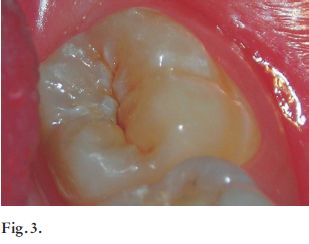

Concomitantemente, Pitts (1) en 1990 afirmó la dificultad que existe de identificar lesiones de caries que involucran tejido dentinario, por el método de inspección visual. Por eso el autor aconseja el uso de radiografías interproximales como complemento en el diagnóstico en la determinación de lesiones que comprometen la dentina, justamente cuando se requiere de tratamientos invasivos (Figs.3, 4 y 5).

Figs. 3, 4 y 5. Se aprecia una lesión cariosa aparentemente incipiente en la pieza 37. En la radiografia se visualiza gran afectación dentinaria, que se correlaciona con la clínica una vez realizada la apertura.